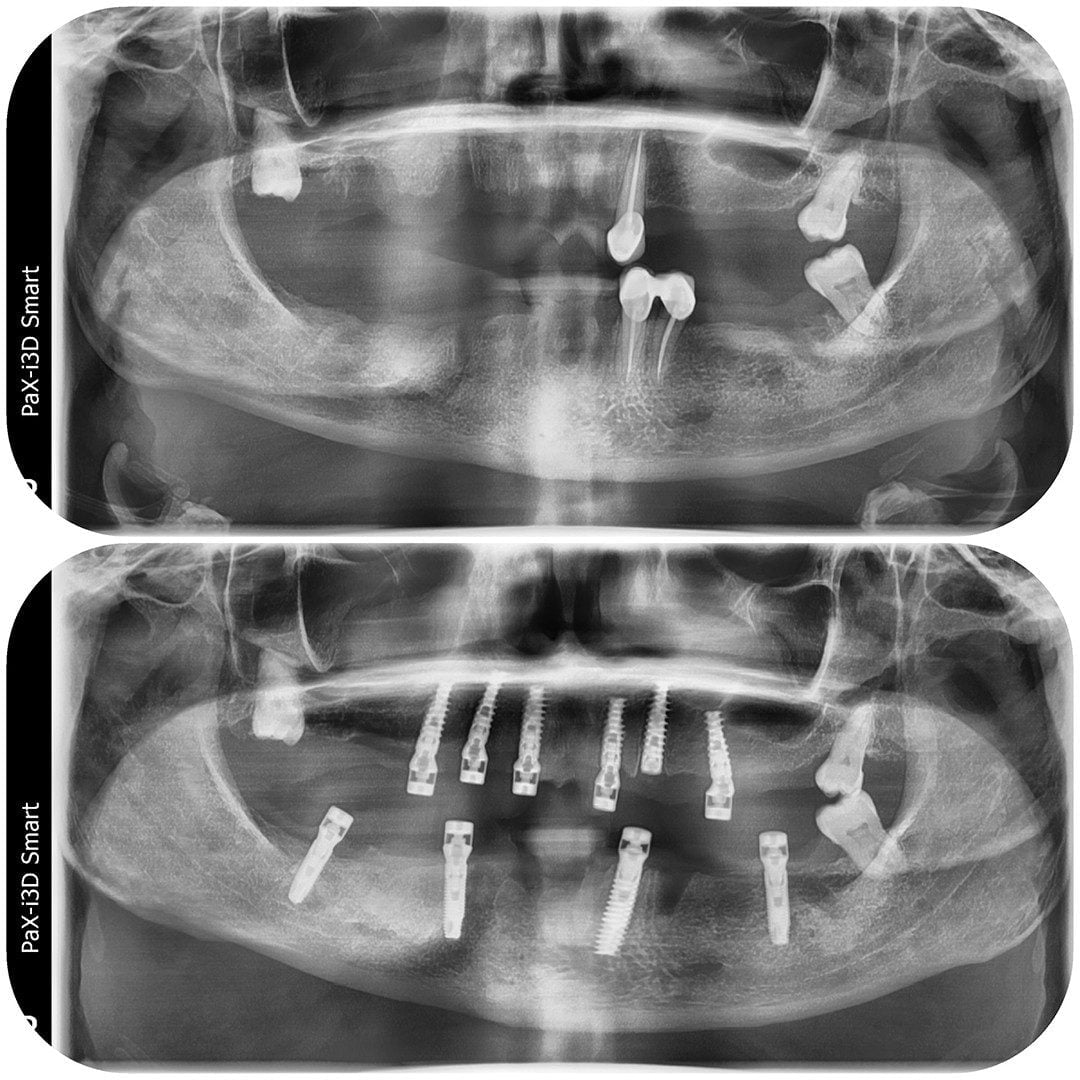

Dinți Ficși în 8-24 de ore pe implanturi dentare cu tehnica All-on-4/All-on-6 este cea mai eficientă și rapidă metodă de restaurare totală a danturii.

Intervenția chirurgicală explicată

Care sunt etapele până la efectuarea intervenției de dinți ficși

- Intervenția chirurgicală